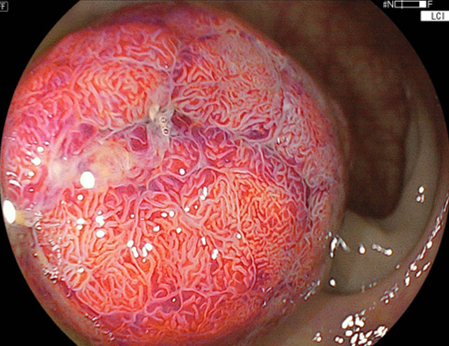

LCIモードにおける弱拡大観察画像

先ほどの反対側の観察では、不整な微細表面構造が

認められます。よって術前診断では高異型度腺腫

(こういけいどせんしゅ)~粘膜内癌(ねんまくないがん)

を想定しました。